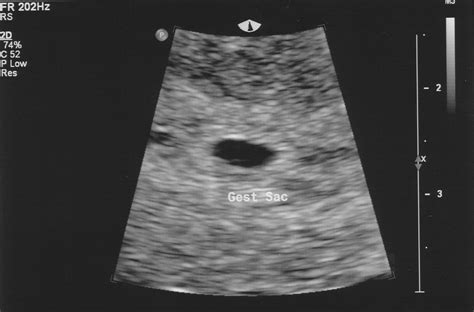

• baby at 4 weeks ultrasound

• baby at 4 weeks pregnant

• baby at 4 weeks gestation